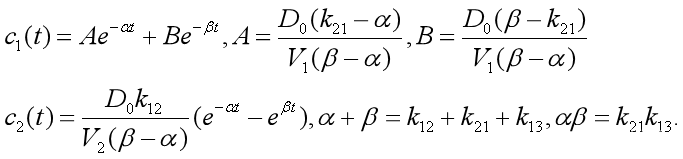

【4.3】在【4.6】条件下得到的特解为 【4.7】

【4.7】

其中A1和B1可以由c1(0)=0,c2(0)=0,B2,A2共同确定。